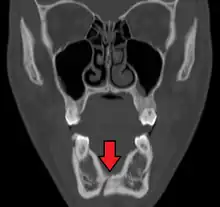

Panoramic radiography

Panoramic radiographs are tomograms where the mandible is in the focal trough and show a flat image of the mandible. Because the curve of the mandible appears in a 2-dimensional image, fractures are easier to spot leading to an accuracy similar to CT except in the condyle region. In addition, broken, missing or malaligned teeth can often be appreciated on a panoramic image which is frequently lost in plain films. Medial/lateral displacement of the fracture segments and especially the condyle are difficult to gauge so the view is sometimes augmented with plain film radiography or computed tomography for more complex mandible fractures.

Research has shown that panoramic radiography is similar to computed tomography in its diagnostic accuracy for mandible fractures and both are more accurate than plain film radiograph.[12] The indications to use CT for mandible fracture vary by region, but it does not seem to add to diagnosis or treatment planning except for comminuted or avulsive type fractures,[13] although, there is better clinician agreement on the location and absence of fractures with CT compared to panoramic radiography.[14]

Panoramic radiograph of a simple mandible fracture of the right mandibular body, minimally displaced. Note that the teeth to the left of the fracture do not touch- lateral oblique image demonstrating a fractured mandible.